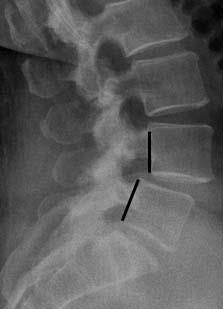

X-ray showing spondylolisthesis

This X-ray taken from the side shows a pars fracture (arrow) and the resulting spondylolisthesis.